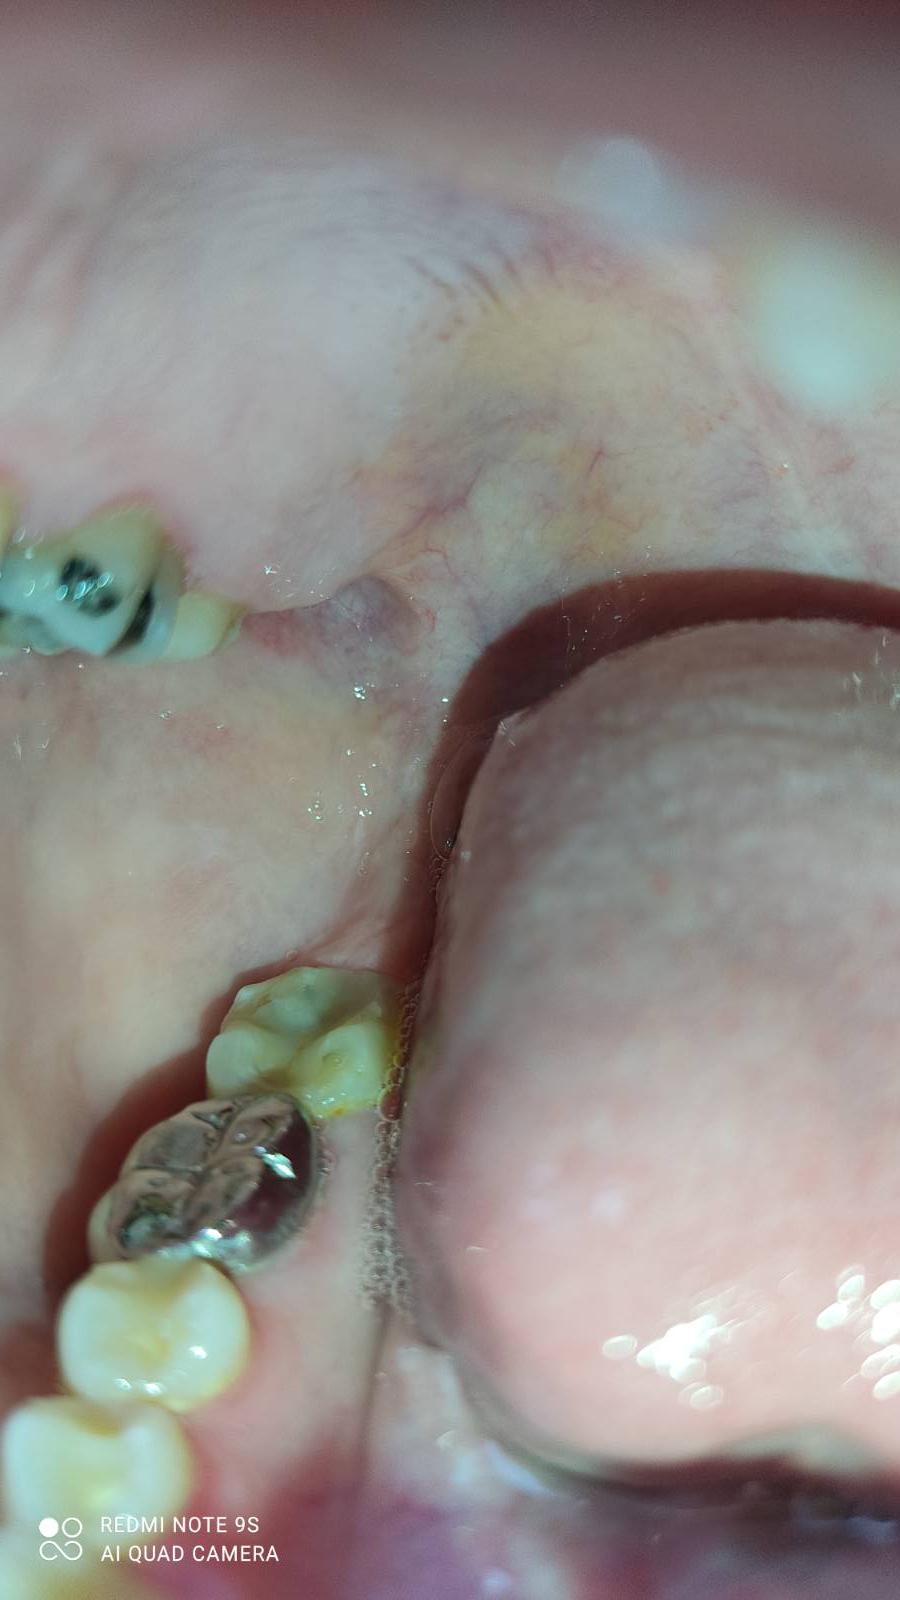

ฟันสึกกับฟันสั้นดูยังไงคะ

แบบนี้คือสึกแล้วใช่ไหมคะ

ฟันกรามข้างในสุดด้านล่าง